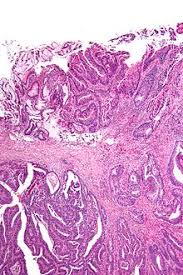

What Do Clear Margins Mean In Cancer : Schematics Illustration Of Tumor Margin Estimation With Siblings And Download Scientific Diagram : Medical college of georgia at augusta university.. After visiting my surgeon he told me the cancer was a stage 2, and not to worry. Before these guidelines, clear margins were considered if >2mm, however, apparently there was no clear evidence that this width of radial margin had a conclusive impact on the local recurrence rate, therefore the new guidelines suggest a reduction of what the clear margin should be. So, if i'm a veterinarian, i'm doing a surgery and i removed the growth and i will submit it to a pathologist, and the pathologist will go around the edge at certain specific locations to see if there are still cancer cells at the edge of the submitted specimen. They are graded r0 for cancer free, r1 for microscopic tumour, ie they can identify some cancer cells and r2 for visible tumour. The goal of a surgeon is to have clean margins, meaning the pathologists cannot find cancer in a sample of the resection margin.

This results in a cure rate of 95% and 92% for primary bcc and scc, respectively, however margins may depend on the location of the lesion, size of the lesion and histopathology of the lesions. But he did get it all. Positive margins mean that cancer cells are found at the edge of the material removed; The pathology report may also say how wide the clear margin is along with the distance between the outer edge of the surrounding tissue removed and the edge of the cancer. Close margins are neither positive nor negative.

The margins do not contain cancer cells. Clear margins imply that all of the cancer was removed, but this does not mean it cannot come back. So, if i'm a veterinarian, i'm doing a surgery and i removed the growth and i will submit it to a pathologist, and the pathologist will go around the edge at certain specific locations to see if there are still cancer cells at the edge of the submitted specimen. I sure hope your appointment clarifies your options. Research shows about 1 out of 4 women who have a lumpectomy go on to have a second breast surgery because the margins weren't clear after their first surgery. One can think of this situation as removing an orange where the peel is the capsule of the prostate and the fruit is the cancer. After visiting my surgeon he told me the cancer was a stage 2, and not to worry. When an area of suspicious cells/cancer is removed with clear margins, there were no suspicious cells/cancer at the edge of the surgical margin. The margins were clear, but once my husband and i have decided if we want more children he said the hysterectomy should be done as there is risk w/ ais. A margin is said to be positive when the tumor cells are seen at the inked margin and negative when they are absent or present away from the inked margin. another vague term used frequently by the pathologists is the close margin which implies that tumor cells are lying in the vicinity of excised margin (varies anywhere between 1mm and 5 mm). I am to be honest as confused as you are around what constitutes a good clear margins as it's different in every paper i read and i've. Medical college of georgia at augusta university. Scott shields answered podiatry 29 years experience congratulations:

The margins contain cancer cells. The goal of a surgeon is to have clean margins, meaning the pathologists cannot find cancer in a sample of the resection margin. Clinical judgment should be used in determining the need for further surgery in patients with negative margins less than 2 mm. When an area of suspicious cells/cancer is removed with clear margins, there were no suspicious cells/cancer at the edge of the surgical margin. The goal of cancer surgery is usually to get clean margins, meaning that a pathologist cannot identify any cancer cells on the margins of the sample. A margin is said to be positive when the tumor cells are seen at the inked margin and negative when they are absent or present away from the inked margin. another vague term used frequently by the pathologists is the close margin which implies that tumor cells are lying in the vicinity of excised margin (varies anywhere between 1mm and 5 mm). The margins were clear, but once my husband and i have decided if we want more children he said the hysterectomy should be done as there is risk w/ ais. A positive margin means that cancer cells come right out to the edge of the removed tissue and have ink on them. I sure hope your appointment clarifies your options. We will do 3 month followups w/ paps, hpv, colps and ecc's. New evidence about why clear margins in breast cancer surgery are such good news. Margins more widely clear than 2 mm do not further reduce the rates of recurrence of cancer in the breast and their routine use is not supported by evidence. There is not always agreement on how large of a margin is necessary and sometimes it depends on the type of cancer.

A pathologist studies the tissue removed during surgery under a microscope and determines whether or not the margins contain cancer cells. If your cancer is tricky to diagnose, the pathologist may write extra comments. They are graded r0 for cancer free, r1 for microscopic tumour, ie they can identify some cancer cells and r2 for visible tumour. Clear (also called negative or clean): It will usually contain the type of cancer, tumor grade, lymph node status, margin status, and stage.

A Comprehensive Review Of Surgical Margin In Oral Squamous Cell Carcinoma Highlighting The Significance Of Tumor Free Surgical Margins Kamat M Rai Bd Puranik Rs Datar Uv J Can Res Ther from www.cancerjournal.net The margins were clear, but once my husband and i have decided if we want more children he said the hysterectomy should be done as there is risk w/ ais. A clean margin refers to the edge of a submitted specimen. The area at the edge of the specimen being examined by the pathologist. Clear margins imply that all of the cancer was removed, but this does not mean it cannot come back. Margins more widely clear than 2 mm do not further reduce the rates of recurrence of cancer in the breast and their routine use is not supported by evidence. Negative (also called clean, not involved or clear) margins. No cancer cells are seen at the outer edge of the tissue that was removed (the tumor along with the rim of surrounding tissue). Research shows about 1 out of 4 women who have a lumpectomy go on to have a second breast surgery because the margins weren't clear after their first surgery.

If your cancer is tricky to diagnose, the pathologist may write extra comments. Clean margins in breast cancer surgery. He did not get clean margins since it was actually lying of the renal artery and there was no way to get them. (there's only normal tissue at the edges of the tissue removed from the breast.) More surgery may be needed to get negative. Close margins are neither positive nor negative. Clinical judgment should be used in determining the need for further surgery in patients with negative margins less than 2 mm. You may decide what you want to do then, or you can get a second opinion if that seems like a good idea. If you've had a biopsy, your tumor is small (under 4 cm), and your surgical margins are clear, a lumpectomy may be all the breast surgery you need. I sure hope your appointment clarifies your options. Medical college of georgia at augusta university. Clear margins refer to the tissue around the removed tumour that are cancer free. Positive margins mean that cancer cells are found at the edge of the material removed negative, not involved, clear, or free margins mean that no cancer cells are found at the outer edge close margins are neither negative nor positive other information: